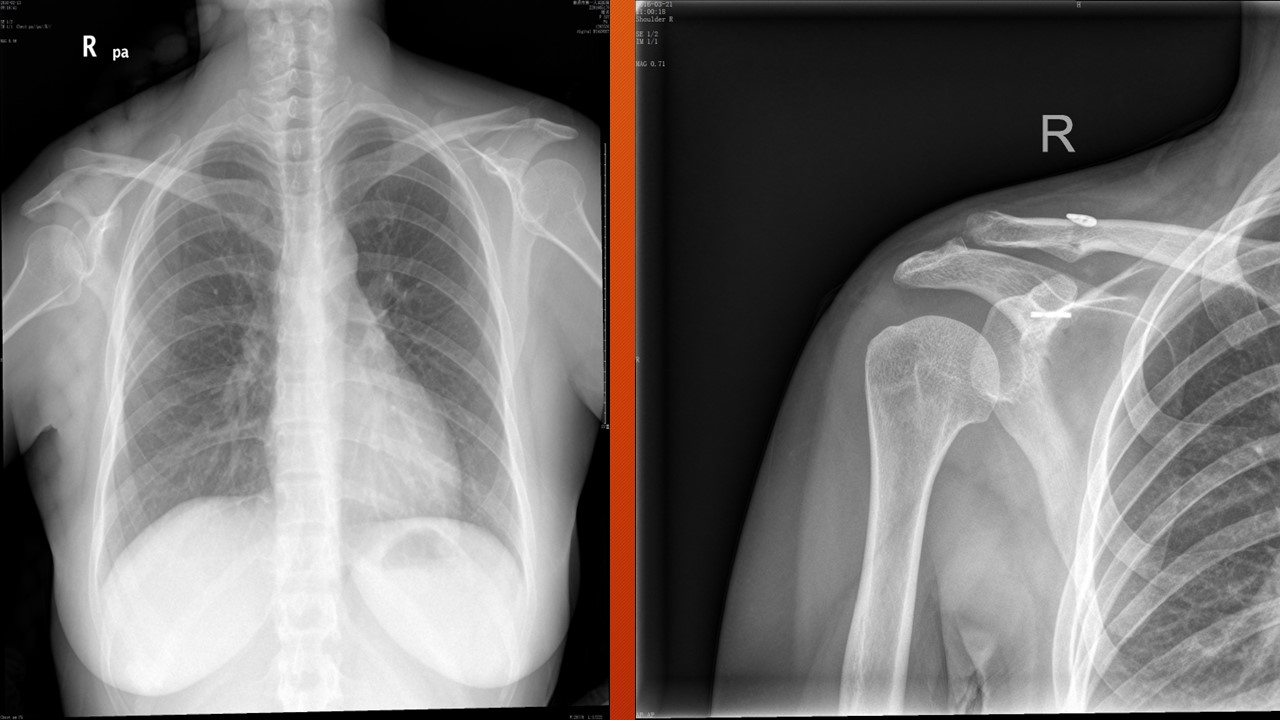

肩锁关节脱位PPT

URIST 形态分型